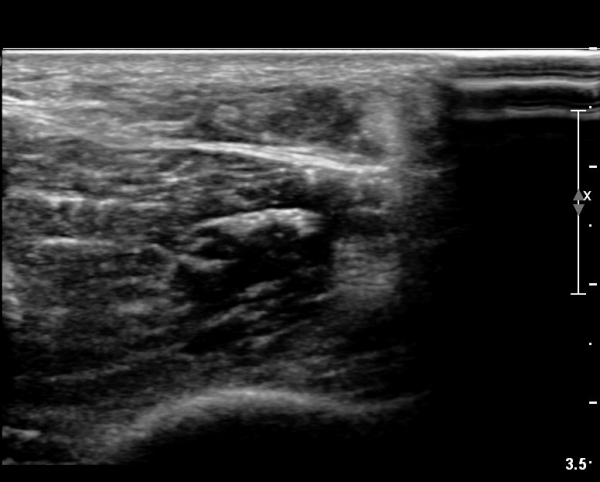

[¹ß¸ñ] simultaneosus tear of GCM and achiles tendon

pain on rt. leg( du: 1 day)

abrupt leg pain developed during foot volleyball

he walk with severe limping with no weight bearing on rt. leg. on examination, there is local tendernes at GCM and achiles tendon, severe pain with ankle dorsiflexion.

ÃÊÀ½ÆÄ °Ë»ç